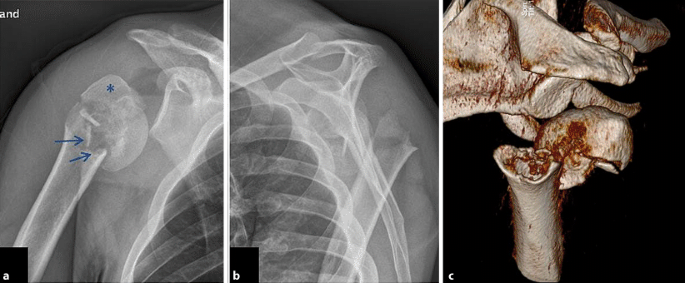

Abb. 5 8 45-jährige Patientin mit einer 3-Part-Fraktur des proximalen... | Download Scientific Diagram